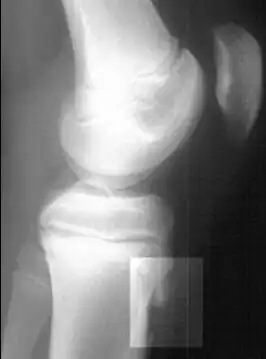

| Radiografia lateral do joelho demonstrando fragmentação da tuberosidade da tíbia, com o tecido superabundante. | |